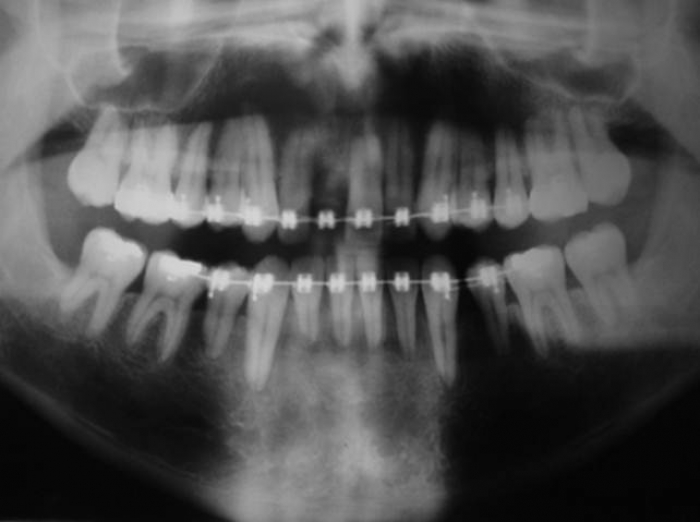

Raio X com implante e prótese provisória